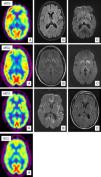

Caso de vECJ. (A) PET-FDG muestra hipometabolismo talámico bilateral y hemisférico izquierdo. (B) FLAIR sin alteraciones relevantes. (C) Aumento de señal en tálamo dorsomedial bilateral en secuencias de difusión. Caso de eECJ. (A) PET-FDG muestra hipometabolismo en núcleos caudado, tálamo y región anterior del putamen. Hipometabolismo región del polo anterior y frontal dorso-medial de predominio izquierdo. (B) Hiperintensidad en la rodilla de la cápsula interna izquierda y ganglios de la base bilateralmente en secuencias FLAIR. (C) Hallazgos similares en secuencias de difusión con hiperintensidad también en tálamo y córtex cingular. Probable caso de eECJ (subtipo MM2). (A) PET-FDG muestra disminución generalizada de la actividad cortical y de ambas regiones talámicas. (B) Hiperintensidad cortical bihemisférico de predominio izquierdo en secuencias FLAIR. (C) Hallazgos similares en secuencias de difusión. Caso de fECJ. (A) PET-FDG evidencia hipometabolismo de la región talámica y ganglios de la base de predominio hemisférico derecho con compromiso de caudado bilateralmente.

Existen muy pocos estudios de neuroimagen funcional en pacientes con vECJ26 (fig. 1). Mediante tomografía computerizada de emisión de fotón único (SPECT) con Tc-99m hexametil propileno amino oxima (Tc-99m HMPAO) se han objetivado alteraciones inespecíficas, tales como hipoperfusión cortical difusa o, por el contrario, más localizada como en región temporoparietal izquierda37. Los estudios de RM con espectroscopia han descrito un aumento de mioinositol (Mi) y una disminución de NAA en el tálamo, y en menor medida en núcleo caudado de estos pacientes38.

Los primeros estudios de RM realizados a pacientes con eECJ mostraron la presencia de una hiperintensidad simétrica en los ganglios basales (caudado y putamen) en las secuencias potenciadas en T2 y DP. Este hallazgo tiene una sensibilidad del 67% y una especificidad del 93% para el diagnóstico de la enfermedad39. Posteriormente se ha comprobado la superioridad de las secuencias FLAIR y sobre todo de la secuencia DWI39–43 (fig. 1). Esta técnica tiene una mayor capacidad de detección de esta enfermedad44 no solamente frente a T2, DP y FLAIR, sino también respecto al EEG (50-78%), y la determinación de las proteínas 14-3-3 (84-94%) y enolasa específica de neuronas (NSE) (73%) en el LCR45,46. La utilización conjunta de FLAIR y DWI aumenta la sensibilidad diagnóstica de la RM al 91% y la especificidad al 95%40. Recientemente Lodi et al43 han sugerido la conveniencia de añadir a los protocolos actuales de RM para diagnóstico de la eECJ el estudio talámico mediante espectroscopía de RM protónica (1H-MRS). Estos autores describen que la combinación del cociente talámico NAA/Cr en la secuencia 1H-MRS (punto de corte ≤ 1,21) con una hiperintensidad en estriado/córtex en secuencias DWI permite clasificar adecuadamente al 93% de los pacientes con eECJ.

En estudios de SPECT y PET con 18-FDG en pacientes con eECJ se ha observado hipoperfusión e hipometabolismo, respectivamente, en la misma localización en la que existe una hiperintensidad en secuencias DWI en RM69 (fig. 1). Henkel et al, en el estudio con mayor número de pacientes publicado hasta el momento69, describen como hallazgo fundamental un hipometabolismo en al menos una región cortical temporal o parietal, junto con hipometabolismo en al menos otra localización de las siguientes: corteza occipital, cerebelo o estructura subcorticales (ganglios basales o tálamo). Este patrón no se aprecia en otras demencias de rápida evolución. Por otra parte en el 50% de los pacientes estudiados en el momento de la realización de la PET no se apreciaron alteraciones en RM, por lo que podría ser una exploración útil en fases tempranas de la enfermedad.

Formas hereditarias (autosómicas dominantes)ECJ familiar (fECJ)Estas formas suponen aproximadamente el 15% de todas las enfermedades priónicas. Se han descrito diversas mutaciones del gen PRNP asociadas a esta patología (codones 129, 180, 183, 200, 210, 219, 220, 232), siendo la más frecuente la E220K. La penetrancia es cercana al 100%. Su diagnóstico puede ser difícil ya que la presentación clínica varía y las características típicas de las enfermedades priónicas no están siempre presentes. Se ha estimado que hasta en un 25% de los pacientes pueden detectarse valores normales en las proteínas 14-3-3 y NSE en LCR45. Los hallazgos de neuroimagen son muy similares a los detectados en las formas esporádicas en la secuencia DWI de RM, con la que se ha visto aumento de señal en los ganglios basales y en la corteza cerebral. La alteración de señal en el núcleo caudado o en el putamen en la secuencia FLAIR descrita tiene una sensibilidad del 87% y una especificidad del 91% en las formas de fECJ. En la secuencia DWI la hiperintensidad del núcleo caudado tiene una sensibilidad del 73% y una especificidad del 100%. Las regiones corticales en las que se observa aumento de señal con más frecuencia son la ínsula, el giro cingulado, la región medial de los lóbulos frontal, parietal y occipital70 (fig. 1).

En casos aislados con esta patología la PET de 18-FDG ha mostrado un hipometabolismo marcado en el cerebelo, ganglios basales, tálamo y corteza cerebral71 (fig. 1). En la SPECT existe una hipoperfusión bilateral en el tálamo, que incluso en algunos casos llega a preceder a las alteraciones detectadas con la secuencia DWI72. Por espectroscopía se ha objetivado una disminución del cociente NAA/Cr con aumento de los niveles de MI en el tálamo73.